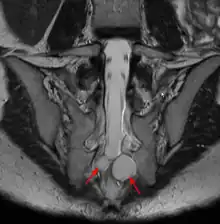

| MRI image showing a Tarlov cyst | |

Tarlov cysts are most commonly located in the S1 to S4/S5 region of the spinal canal, but can be found along any region of the spine. They usually form on the extradural components of sacrococcygeal nerve roots at the junction of dorsal root ganglion and posterior nerve roots and arise between the endoneurium and perineurium.[10] Occasionally, these cysts are observed in the lumbar and thoracic spine.[7] However, these cysts most commonly arise at the S2 or S3 junction of the dorsal nerve root ganglion.[11][12] The cysts are often multiple, extending around the circumference of the nerve, and can enlarge over time to compress neighboring nerve roots, to cause bone erosion.[13] The cysts may be found anterior to the sacral area and have been known to extend into the abdominal cavity. These cysts, though rare, can be found to grow large - over 3–4 centimetres (1.2–1.6 in) in size, often causing severe abdominal pain from compression on the cyst itself as well as adjoining nerves.

MRI, or Magnetic Resonance Imaging, is considered the imaging study of choice in identifying Tarlov cysts. MRI provides better resolution of tissue density, absence of bone interference, multiplanar capabilities, and is noninvasive. Plain films may show bony erosion of the spinal canal or of the sacral foramina. On MRI pictures, the signal is the same as the CSF one.